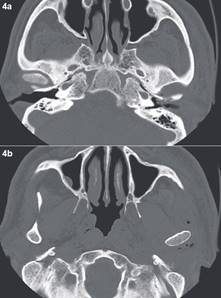

Caso N°2: Paciente sexo masculino 71 años con Diabetes Mellitus tipo II insulino requiriente, refiere que sufrió un traumatismo con elemento contundente en región geniana izquierda de un mes de evolución, posterior al golpe cursa con dolor y aumento de volumen en región mandibular izquierda con disfagia y dislalia. Consulta en múltiples servicios de urgencia, siendo tratado con Amoxicilina con Ácido Clavulánico y Analgésicos no esteroidales (Aines), sin una respuesta favorable. Evoluciona con incremento del dolor y aumento de volumen. Posteriormente cursa con fiebre y compromiso del estado general y 6 días después consulta al servicio de urgencia del hospital. Al ingreso en el servicio de urgencias, se presenta normotenso y afebril con dolor preauricular punzante progresivo. Al examen físico presenta luxación mandibular izquierda con imposibilidad de cerrar la boca, y desviación severa de la mandíbula a la izquierda asociado a un aumento de volumen parotídeo izquierdo presentando una PCR de 290mg/dl (fig. 3). Al día siguiente es evaluado por Cirugía Maxilofacial, donde se presenta febril, confuso, desorientado y con otorrea izquierda. La evaluación por el servicio de Otorrinolaringología constata presencia de exposición ósea y secreción purulenta en oído izquierdo. Se hospitaliza y se inicia antibioterapia empírica con Ceftriaxona y Metronidazol endovenosa, a su vez se realizaron hemocultivos y cultivo de secreción del conducto auditivo externo (CAE) izquierdo, siendo estos negativos. La TC evidencia fractura de pared anterior del CAE, luxación de articulación témporo-mandibular (ATM) izquierda y con un proceso inflamatorio extenso en el espacio masticatorio izquierdo (Fig.4). Evoluciona desfavorablemente, con disfagia, requerimientos de oxigenoterapia, aumento de volumen facial y cervical progresivo, elevación de parámetros inflamatorios y coagulopatía. Se modificó la terapia antibiótica a Sulbamox y se tomó una TC con contraste que muestra un aumento de volumen cervical difuso de espacio masticatorio, parafaringeo y bucofaríngeo con abundantes burbujas de aire (Fig.5). Al día siguiente se realizó aseo quirúrgico en pabellón de urgencia de espacios cervicales profundos; intubado con traqueotomía, mediante acceso preauricular, se realizó la exploración de ATM izquierda con extensión cervical e instalación de drenajes. Se realizaron cultivos de las cavidades abscedadas. Posterior al pabellón ingresó a la unidad de cuidados intensivos (UCI), sedado con asistencia ventilatoria mecánica y se continuó el manejo del shock séptico, con apoyo de drogas vasoactivas por al menos 48hrs. Evolucionó con fascitis necrotizante en región cervical anterior y posterior izquierda, sin avanzar a mediastinitis; además de una hipertensión arterial concomitante. Se realizaron otros 3 aseos quirúrgicos en pabellón y nuevos cultivos microbiológicos. Luego de 12 días en la UCI regresa a sala donde presenta una mejoría sostenida y progresiva. Los cultivos mostraron Staphilococus Epidermidis, Cándida y bacilos Gram +, que fueron tratados con antibioterapia endovenosa (Vancomicina, Sulbamox y Fluconazol) hasta completar 6 semanas siendo dado de Alta a los 2 meses desde el ingreso sin signos de infección y parámetro inflamatorios normales (Fig. 6). Durante este tiempo fue evaluado y tratado por los equipos de cirugía maxilofacial, otorrinolaringología, infectología, medicina y fonoaudilogía.